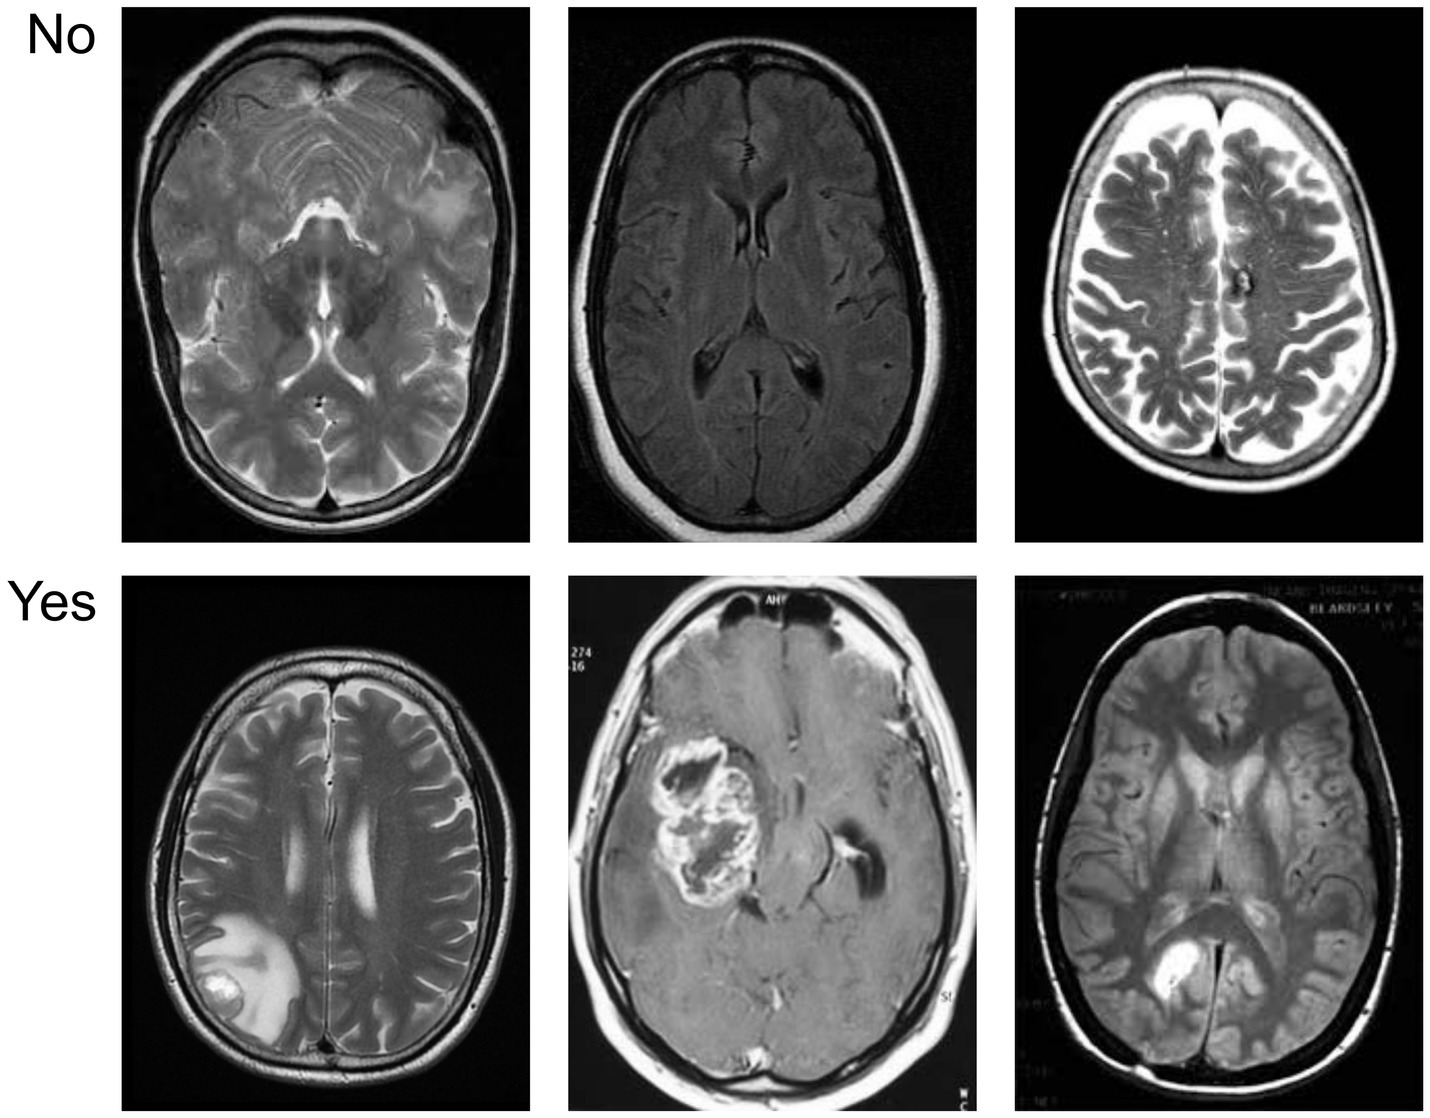

Figure 5 provides a visual overview of the dataset used in our experiments, distinguishing between cancerous and non-cancerous MRI brain scans. Our CNN effectively captured these differences in structural patterns and intensities for classification.

Figure 5

Sample visualization of the MRI dataset illustrating differences between tumor-positive and tumor-negative brain images.